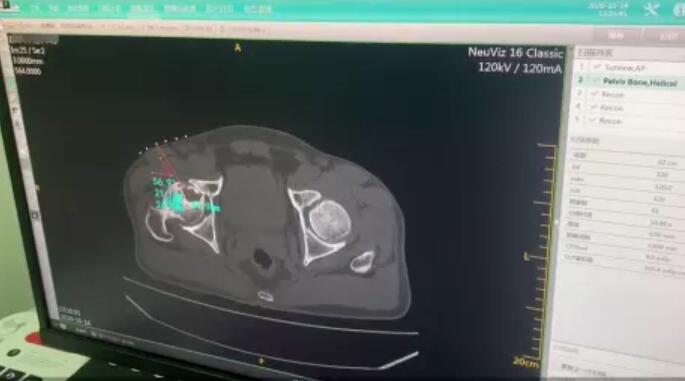

根据生物学和细胞学的相关理论研究,将具有活性成分的成骨细胞及促进成骨细胞生殖分裂的相关生长因子和细胞因子,在CT精准定位的前提下,微创穿刺种植到坏死囊变区,为坏死囊变区提供新骨生成所需的足量成骨细胞种子与相关营养物质,帮助坏死区再生新骨获得精准修复,从而很好的预防塌陷的发生。

CT辅助、精准定位坏死灶,确定穿刺路径

在专业CT检测下,精准定位坏死灶,确定并计算好微创穿刺位置与角度。确保治疗的精准有效以及手术的安全。